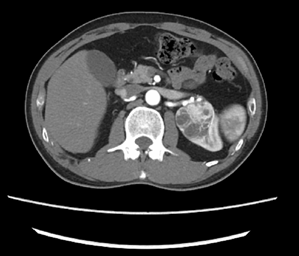

近日,家住金华的胡先生(化名)遇到了重大危机:人到中年,平时身体还算健康,正是事业黄金期,家中的顶梁柱,在一年一度健康体检时,发现左侧肾脏上多了一颗“定时炸弹”。 这枚“炸弹”悄无声息地盘踞在胡先生的左肾上,沉默地挤占、延伸着,竟已超过半个肾脏的大小。这消息对全家来说,不啻惊雷。 当地医院的医生告诉胡先生,这枚肿块的位置较深,手术难度较大,可能无法保留左肾。胡先生怀着沉重的心情和家属讨论后,决定到浙江大学医学院附属第二医院泌尿外科寻求治疗。 (胡先生的左肾肿瘤) 浙大二院泌尿外科的裘益青主任医师接诊了胡先生。面对胡先生的情况,裘医生仔细阅片,告诉胡先生他的年龄不大,肾功能尚可,左肾肿瘤形态和密度考虑恶性肿瘤,而且体积较大,位置较深,位于肾门,需行保肾的肿物切除手术,手术难度较大,建议使用达芬奇机器人辅助手术。 在于家人讨论后,胡先生决定听从裘医生的建议,接受手术治疗。 03一觉醒来剥除“定时炸弹” 术前,裘医生在科室进行了手术讨论,决定了机器人辅助下腹腔镜经后腹腔的手术方式。手术开始,裘医生充分游离左肾周筋膜,开阔视野,暴露肾脏中上极背侧肾门部约4.5cm的那枚“定时炸弹”,它突出肾脏表面,盘踞肾门,血管包绕与周围组织明显粘连,若要完整剥除必定是一场硬战。 裘医生继续沿肾脏表面游离暴露左肾动脉,准备充分后,开始阻断。接下来就是争分夺秒地剥除肿块,因为考虑恶性肿瘤,必然要万分谨慎,不能破坏一点肿瘤的完整性。好在准备充分,视野暴露清晰,裘医生熟练而冷静地剥除肿块,缝合创面。 、 仅仅用时15分钟。阻断的肾动脉再次回复血供,“定时炸弹”已经被“收缴”,术野没有明显出血。 一觉醒来,胡先生肾上的“定时炸弹”已经取下,术后第二天就下床活动,很快就恢复出院了。术后病理报告为肾透明细胞癌。 肾癌是泌尿系统常见的肿瘤,仅次于前列腺癌和膀胱癌,却是泌尿系统致死率最高的恶性肿瘤,其发病率占成人恶性肿瘤的2%~3%。肾癌的治疗和预后与其病理类型和肿瘤分期明显相关,肿瘤发现越早,保留肾脏和功能的机会越大,治疗效果越好。早期肾癌多无临床症状,是通过健康体检或其他检查偶然发现,此类目前约占60%。明显症状出现比如血尿、腰痛、腹部肿块等往往提示晚期肾癌。 所以,早期发现肾癌,主要依靠健康体检,彩色多普勒超声作为初筛检查,超声发现异常时,需要进一步完善增强CT或MRI检查,以帮助医生诊断及对肿瘤进行分期,选择最佳的治疗方式。 专家简介 裘益青 泌尿外科主任医师 熟练掌握腹腔镜下(含机器人辅助)根治性膀胱切除术、保留性神经的根治性前列腺切除术、保留肾单位肾癌手术等。

02 肿瘤体积大 位置深 达芬奇机器人登场